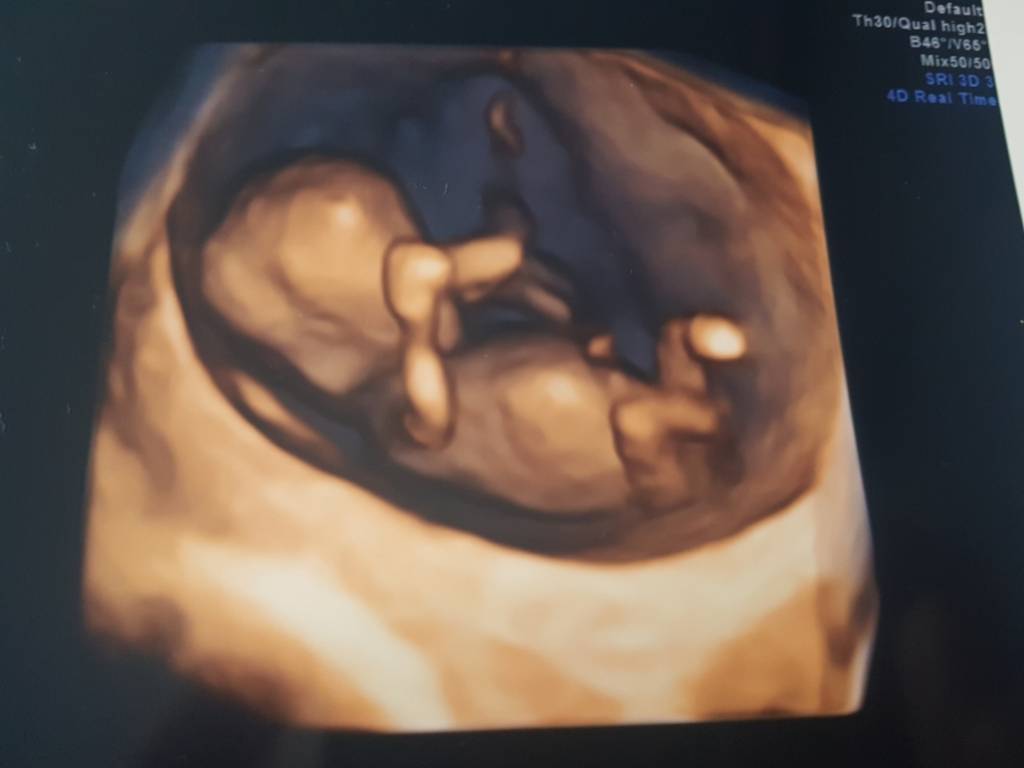

cudowna wiadomość że dzieciątko zdroweDziewczyny, jest dobrze [emoji4] maluch ma teraz 5,5cm [emoji173] serduszko ladnie bije 159bpm, pepowina trojnaczyniowa [emoji7]

Aaa co do plci na podstawie wyrostka wydaje sie ze to dziewczynka [emoji7] ale Pani Dr mowi ze ten wyrostek taki nie calkiem lezacy, wiec dzidzius moze nas jeszcze zaskoczyc i w ktoryms momencie sie pojawic siusiaczek [emoji4]